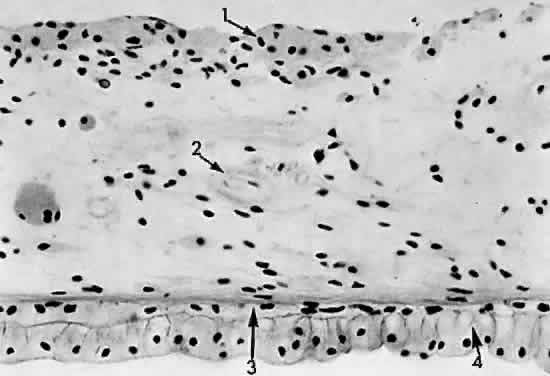

The pars plicata features approximately 80 radially placed ridged fronds representing the ciliary processes or crests (Fig. 10). The ciliary processes begin at the posterior border of the iris root and protrude into the posterior chamber. The processes have a vascularized connective tissue core covered by two layers of epithelium: a surface, nonpigmented, “secretory” cuboidal epithelium and an underlying pigmented epithelium layer (Figs. 11 and 12). The pigmented epithelial cells and the nonpigmented epithelial cells of the ciliary body are arranged apex to apex. The basement membrane of the pigmented epithelium faces the ciliary body stroma, whereas the basement membrane of the nonpigmented epithelium (internal limiting membrane) lines the posterior chamber and faces the vitreous and lens. During secretion of aqueous, nutrients from the capillaries in the ciliary processes pass through the endothelium and the basement membrane into the stroma, through the basement membrane of the pigmented epithelium to the pigmented epithelial cell, to the nonpigmented epithelial cell, and finally through its basement membrane (which forms the internal limiting membrane of the ciliary process). Tight junctions between the pigmented and nonpigmented epithelial cells inhibit leakage of nutrients between the cells. Aqueous humor formation is induced by active “secretion” by the inner cell layer (probably associated with the endoplasmic reticulum and the Golgi apparatus). Zonulae occludentes adjacent to the apical borders of the nonpigmented epithelial cells fill the lateral intercellular spaces to preserve the blood-aqueous barrier of the ciliary body.

Fig. 11. Ciliary processes: 1, capillary; 2, nonpigmented (secretory) epithelium; 3, pigmented epithelium (× 195, KEI 8982B).

Fig. 12. Ciliary process epithelium:1, nonpigmented epithelium; 2, pigmented epithelium (× 580, KEI 8982B).